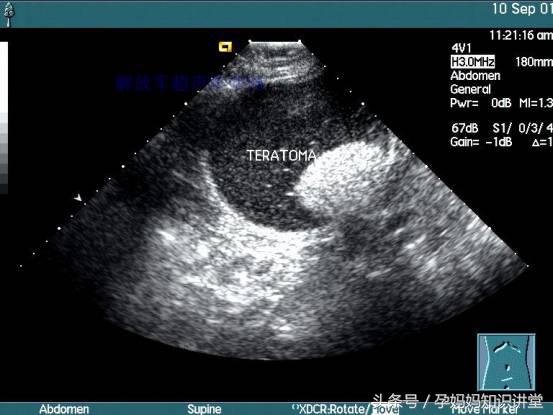

发现胎儿畸形:孕18-20周胎儿各个器官已发育成形,此时可看出胎儿是否有畸形,如胎儿肢体畸形、内脏畸形、神经管畸形、无脑儿、脊柱裂、小头畸形等。使用分辨清晰的B超仪,更可诊断出胎儿的肢体畸形、唇腭裂畸形等。在此期间发现胎儿畸形、容易终止妊娠。